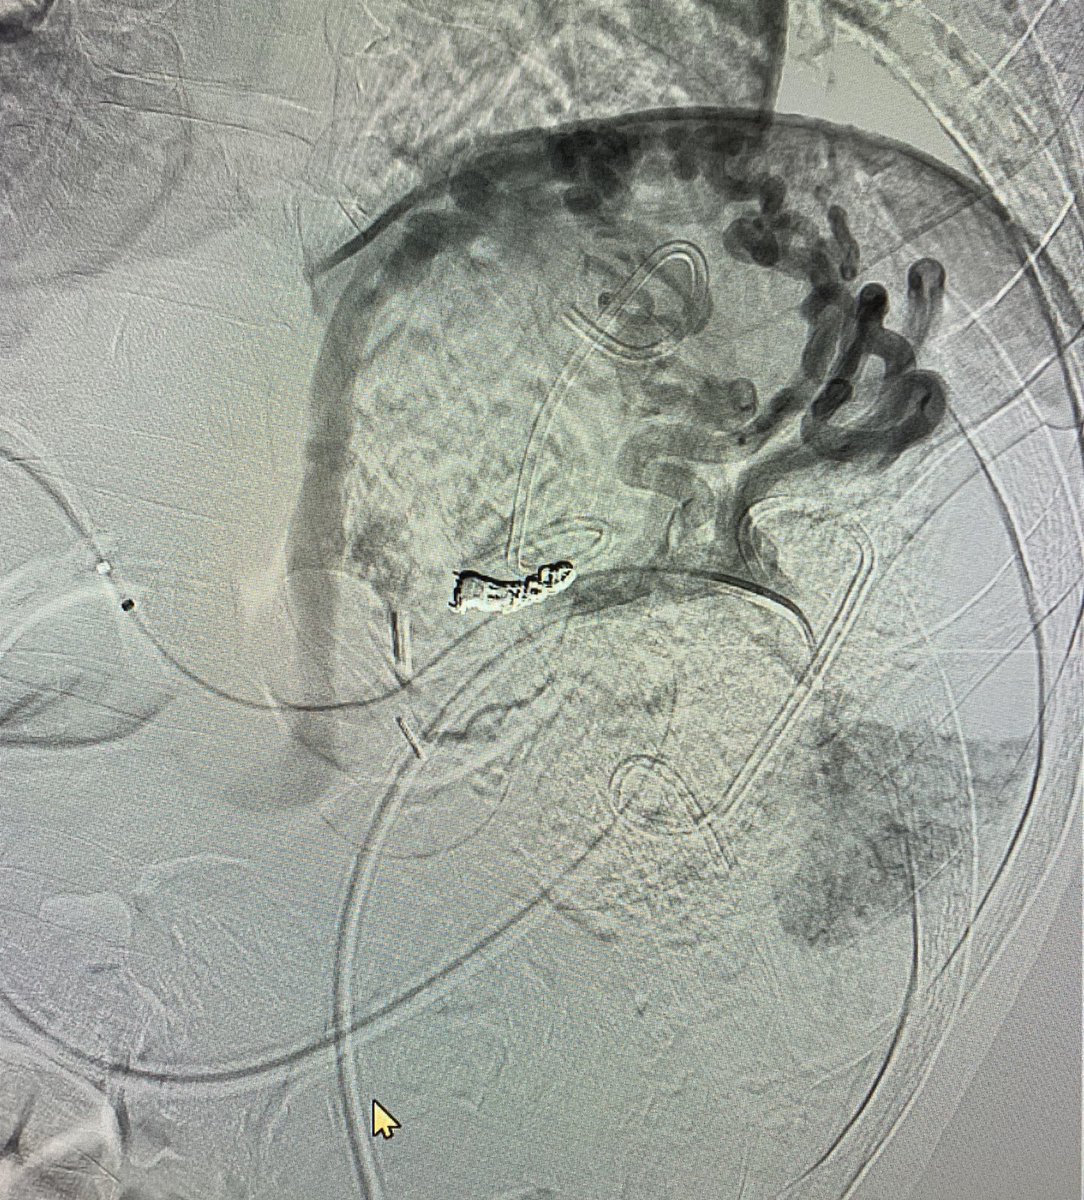

56 Y O known Chronic Liver Disease with Isolated Gastric Varices. Treated by

#Balloon#Occlusion Transvenous#Obliteration and#VascularPlug Placement#Intervention#Radiology#Makkahpic.twitter.com/0eup4cuY7x